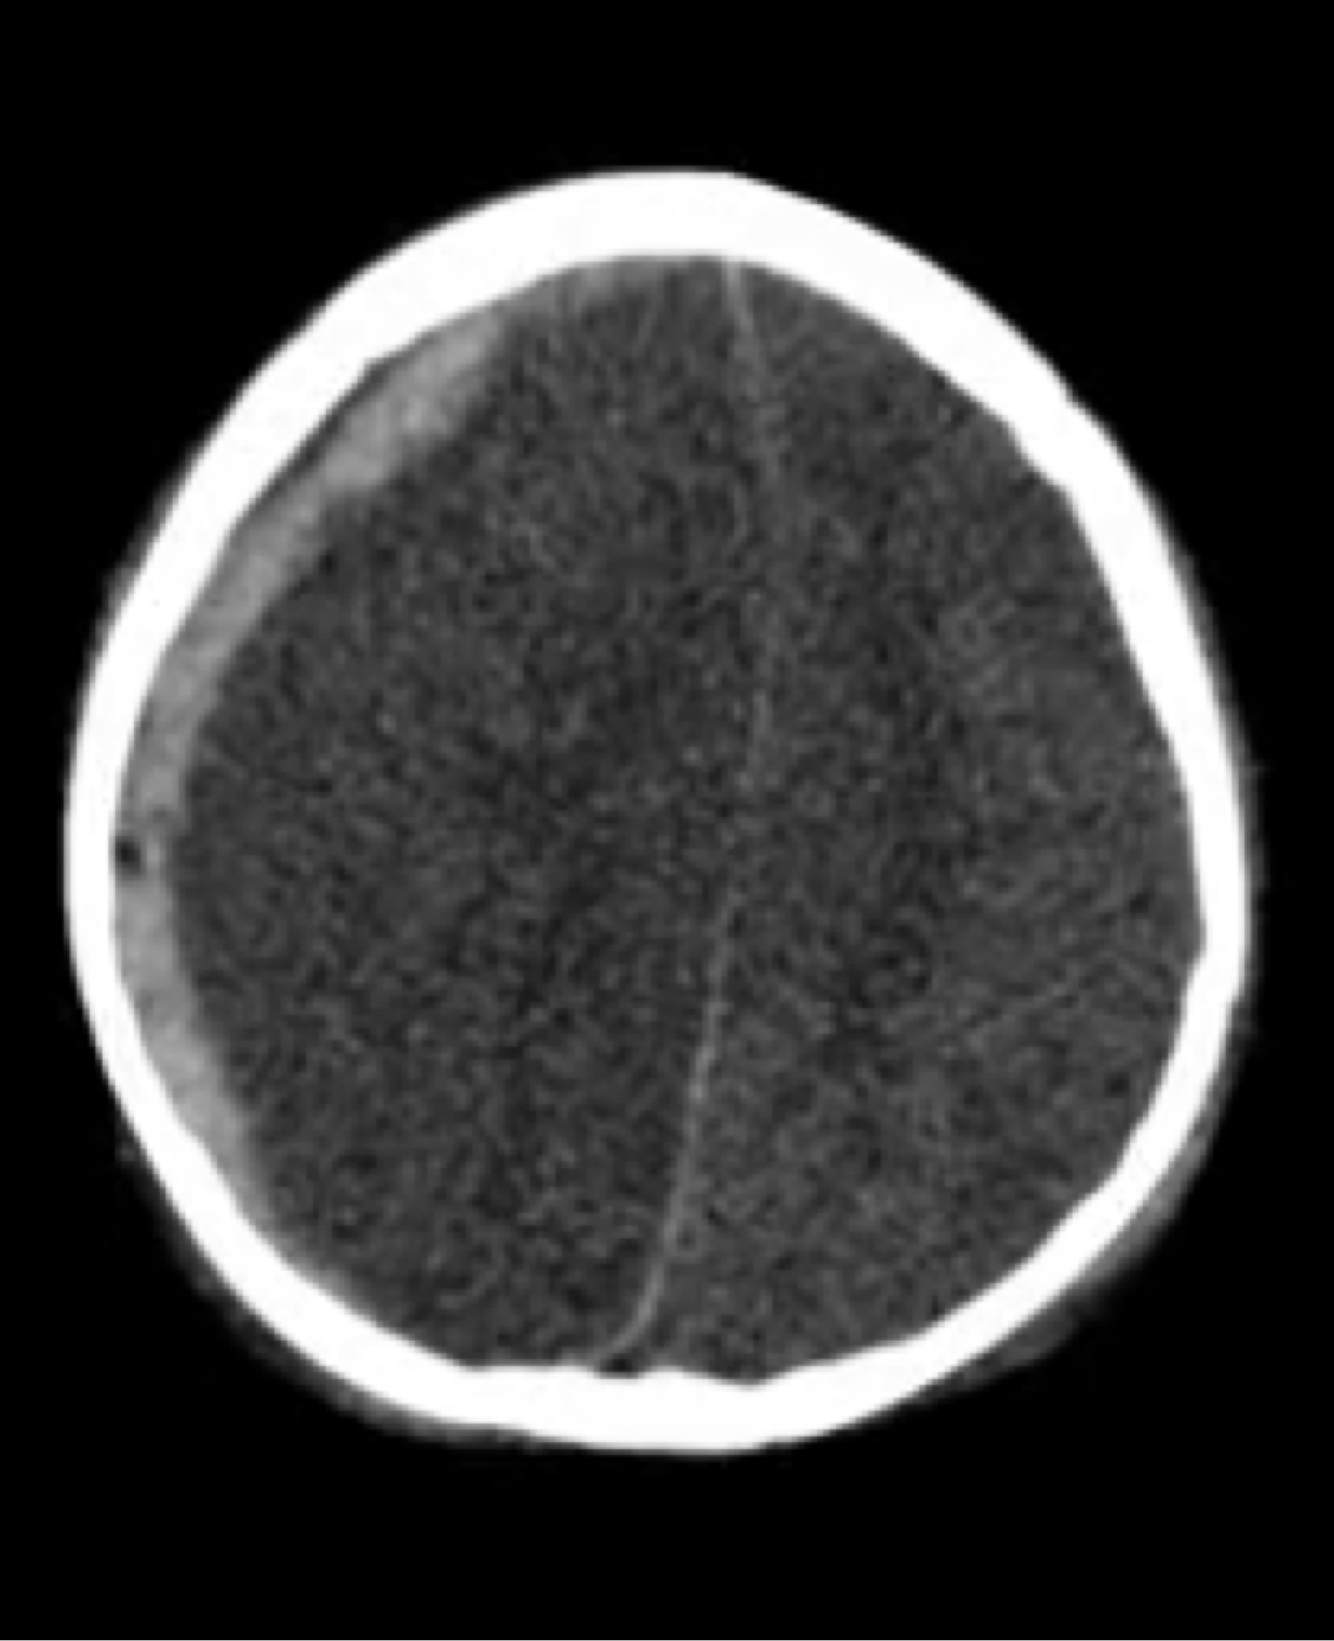

Q

Qual o tipo de fratura a seguir?

A

Aberta.

As bolhas de ar indicam pneumoencéfalo.